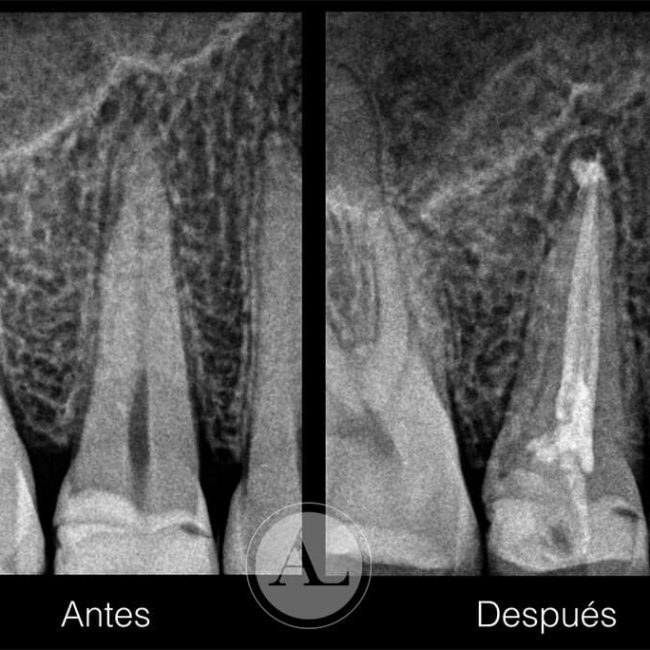

La endodoncia, conocida popularmente como “matar el nervio”, consiste en eliminar la pulpa dental afectada por caries profundas, traumatismos o infecciones, limpiando y sellando el interior del diente para conservar su estructura. En nuestra clínica dental en Córdoba realizamos tratamientos de endodoncia en Córdoba capital con microscopio dental, lo que nos permite una mayor precisión y éxito a largo plazo.

En Dental Lucena y Morales realizamos diferentes tipos de endodoncia según la pieza dental afectada: